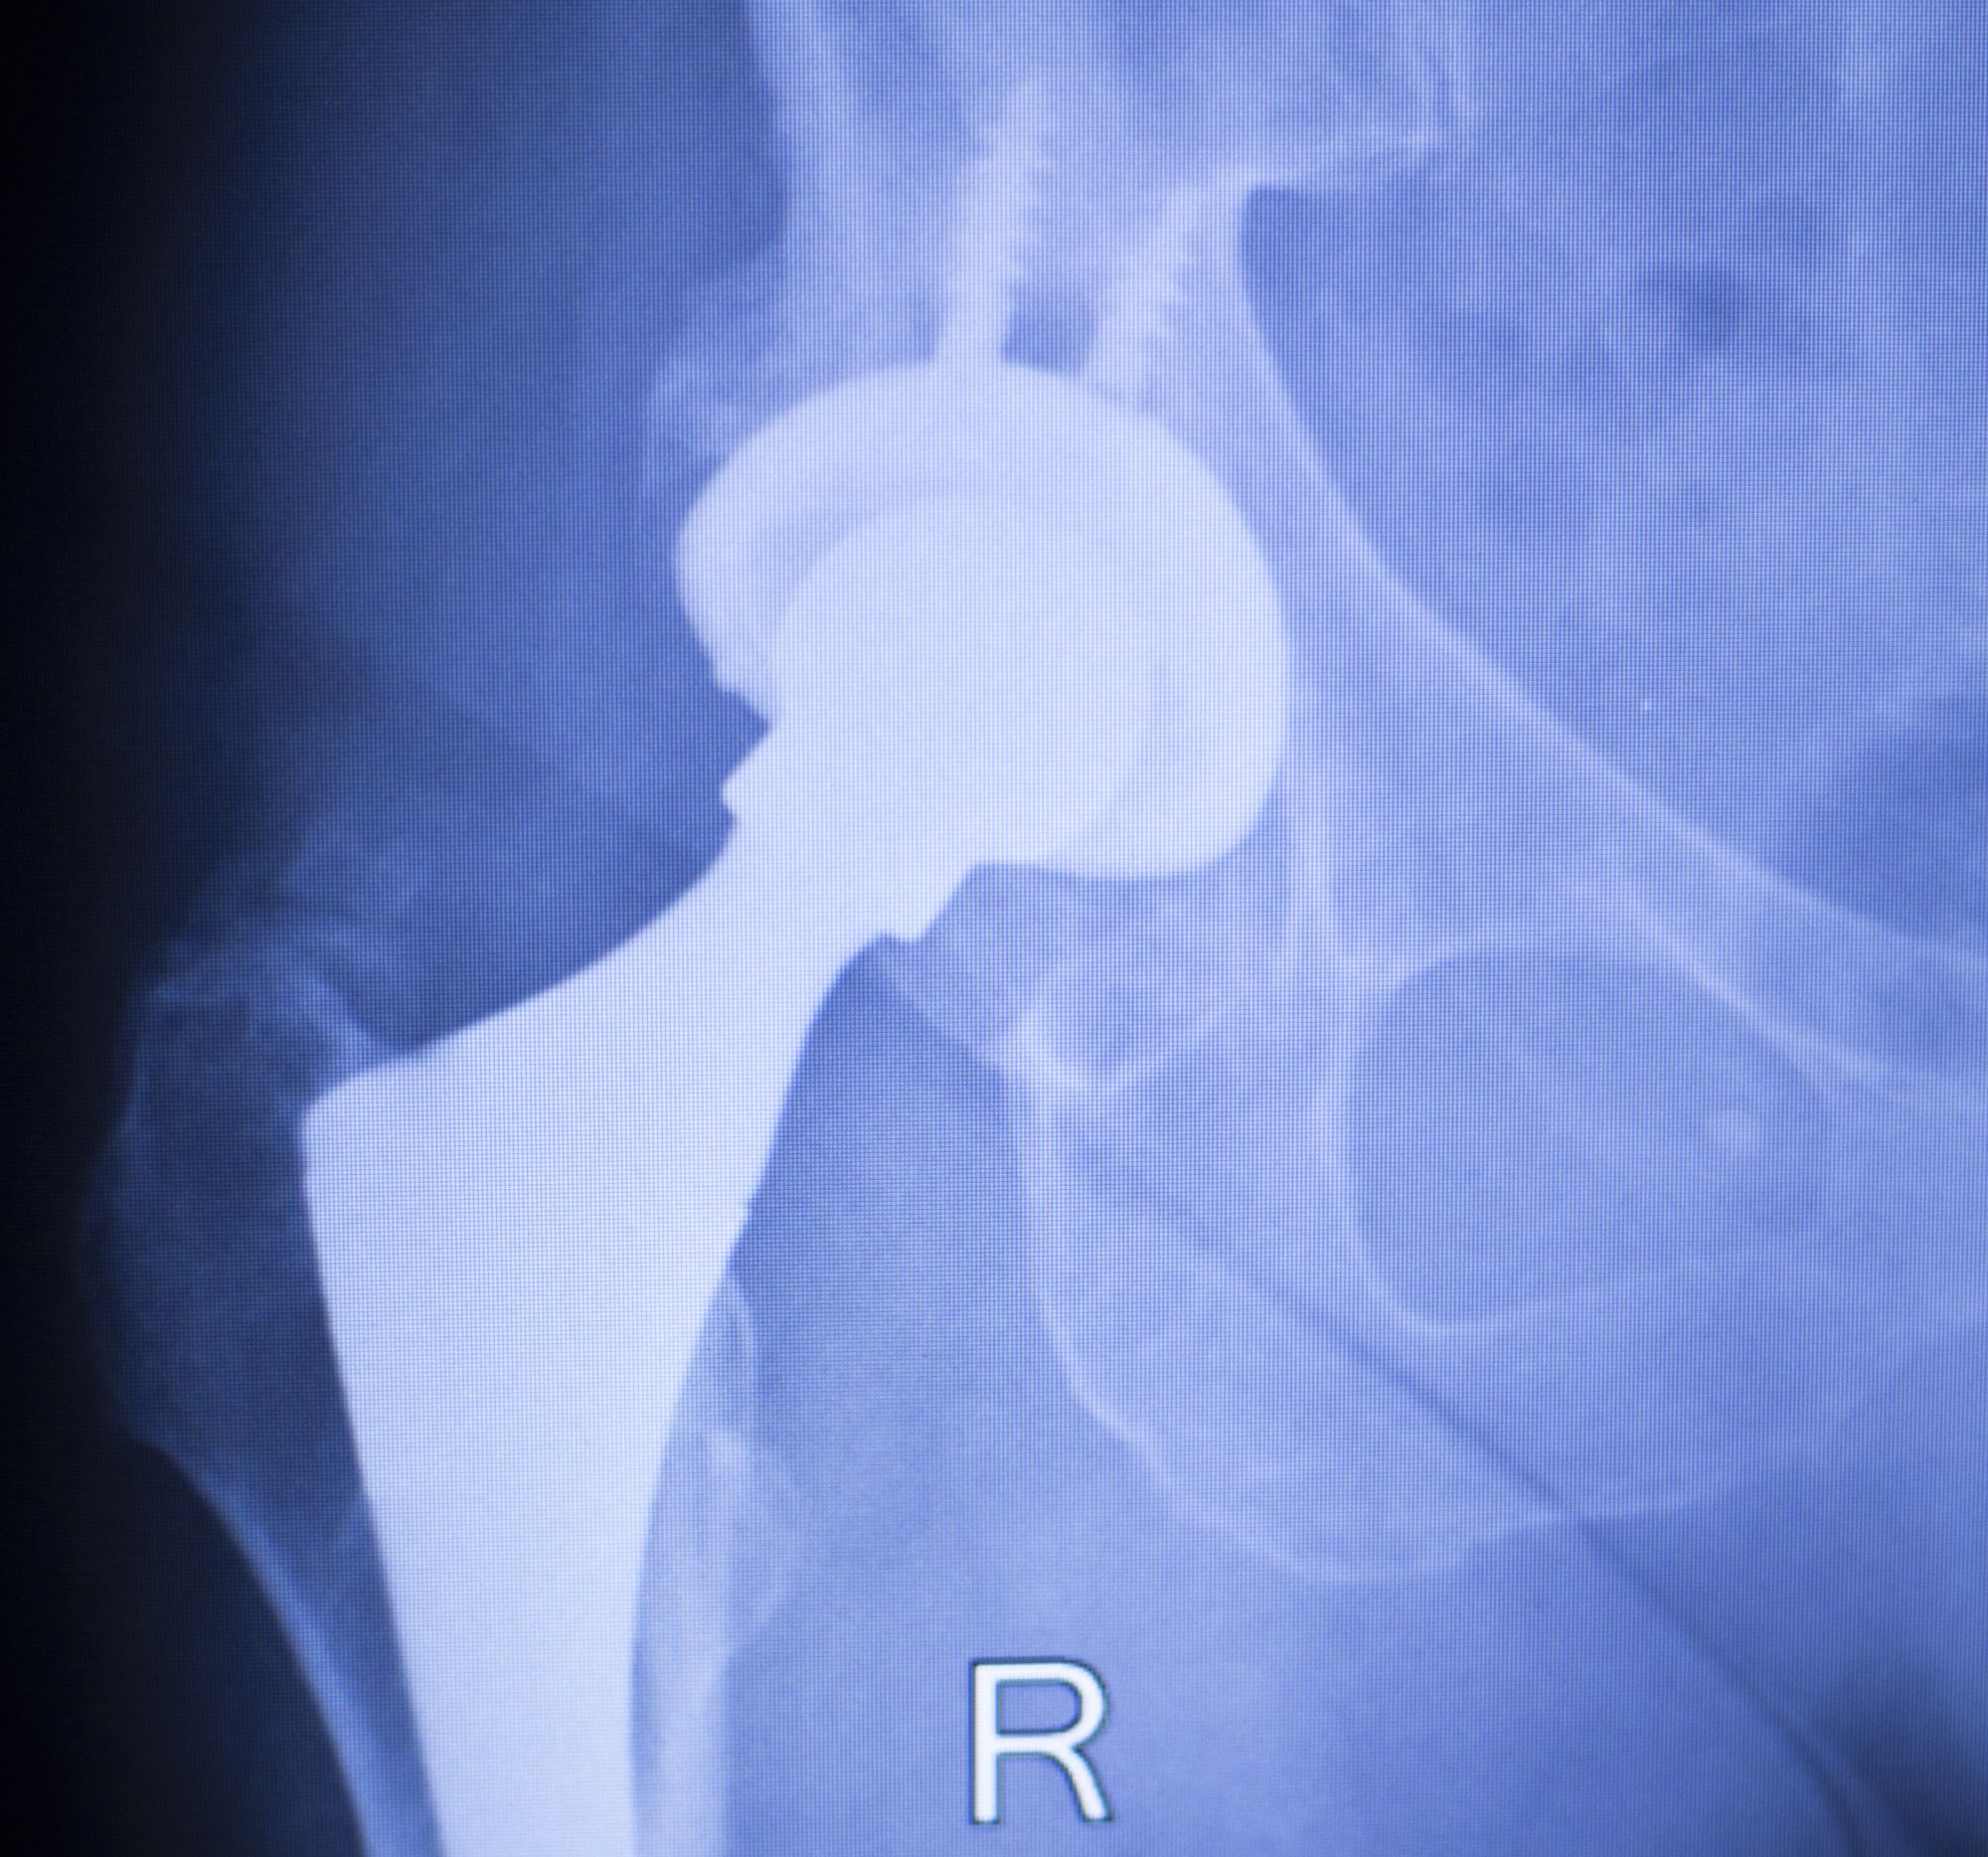

Stryker-Accolade-hip-implant-recallFallout from the Stryker Accolade hip implant recall continues as patients suffering from the failed devices file lawsuits.

The Stryker Corporation is one of the world’s biggest manufacturers of medical equipment and orthopedic products. The Accolade hip implant models made in 2009, 2011 and 2013 were recalled due to packaging and manufacturing problems.

The Stryker Accolade hip implant recall is in part because of the risk of metallosis, also known as metal poisoning.  The hip parts are made of a titanium alloy that can corrode or cause tiny pieces of metal debris to shave away when used with cobalt chromium femoral heads.

The Stryker Accolade is accused of spontaneously dissociating, meaning the femoral head becomes loose from the stem. This can happen so suddenly that a patient who has had no previous indications of a problem can suffer catastrophic failure with no notice. In these cases, the patient needs immediate medical help and, most likely, revision surgery to replace the implant.